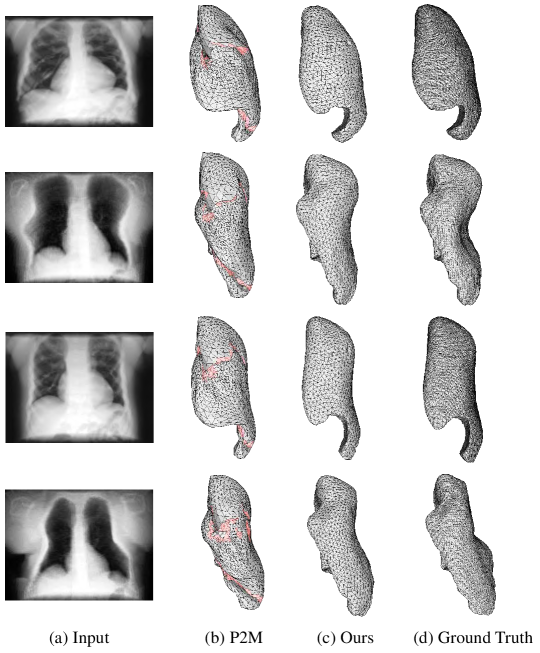

Comparison with Pixel2Mesh [50]: Intuitively, according to the Pixel2Mesh (P2M) experiment setting, we first use their network to predict a single lung from a single-view input image.

We train P2M on our synthetic dataset following their training details. The quantitative evaluation result is shown in Tab. 1. We fairly set our output mesh vertex number to be the same as the output of P2M network (i.e., 2466). The CD and EMD are both computed between the uniformly sampled 1024 points from the prediction and ground truth such that the comparison can be made not only between the single lung reconstruction from P2M and our network, but also between the lung pair reconstruction (see Tab. 2) and single lung reconstruction of our network. From Tab. 1, our network outperforms P2M on all metrics.

Method CD EMD F-score (ϵitalic-ϵ\epsilon / 1.5ϵ1.5italic-ϵ1.5\epsilon) IoU HD (Mesh) P2M (Left Lung) 2.4609 76.2620 0.5983 / 0.7799 0.7190 0.1300 Ours (Left Lung) 1.7018 57.0856 0.7293 / 0.8910 0.8352 0.0672 P2M (Right Lung) 2.3399 69.7205 0.6111 / 0.8014 0.7661 0.1022 Ours (Right Lung) 1.7300 59.9497 0.7293 / 0.8892 0.8423 0.0786

We also present the qualitative comparison results in Fig. 5 and Fig. 6. Both (P2M and our) networks yield predictions of smooth surface but our model performs better in well preserving the mesh surface geometry without non-manifold issue. The reason may be that the input single-view 3D-CBCT projection image is essentially different from a 2D natural input image. P2M has no mechanism to deal with the ambiguity caused by such ill-posed problem like PSGN. However, our network have more specific templates to start with so as to rule out some uncertainties or local minima, while the initial ellipsoid template in P2M network is too general for this task; and how to modify their network to fit for an initial lung shape is beyond the scope of this work.

Refer to caption

Figure 5: Qualitative comparison with P2M and our method on left lung model. Our results generate meshes with no non-manifold issue, while the results from P2M have self-intersections (highlighted in red).

Figure 6: Qualitative comparison with P2M and our method on right lung model. Our results generate meshes with no non-manifold issue, while the results from P2M have self-intersections (highlighted in red).